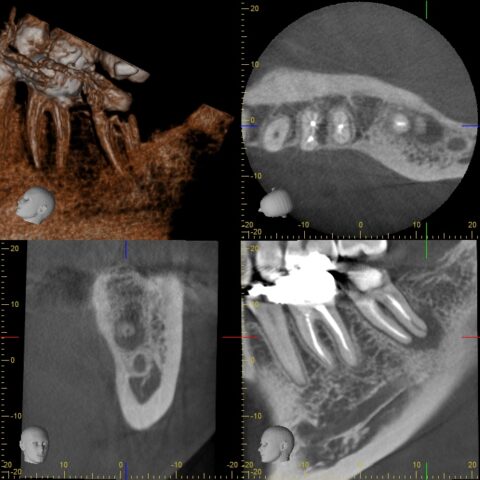

before

after

| 症状 | 検査をしてほしい |

|---|---|

| 年齢・性別 | 30代 女性 |

| 治療期間・回数 | 治療回数 約1ヶ月 |

| 治療方法 | 精密根管治療+PGA Cr |

| 費用 | 約20万 |

| 治療前の注意点 | ラバーダム防湿は必須 |